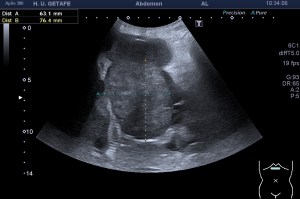

La imagen 3 y 4, como son tan nítidas, puedes ver como el quiste de Baker no es un quiste de Baker simple, la pared es grosera, tiene septos y ecoestrusturas que hacen pensar que el quiste ha podido sufrir algún sangrado. Hay que descartar la formación de lesiones sólidas o polos sólido en los quistes (usando doppler), por norma general, en todos aquellos quistes que estudiemos, en otras localizaciones, por ejemplo, en la mama, en el abdomen, etc.